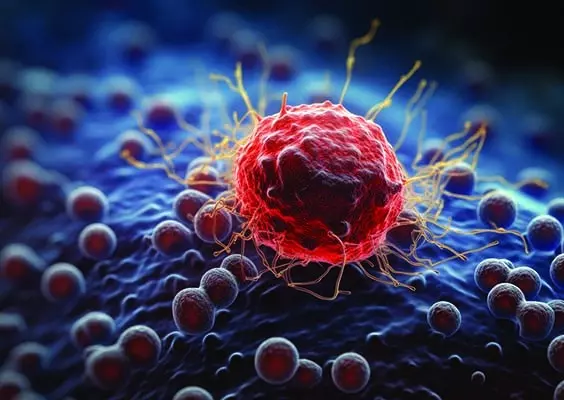

W grudniowym wydaniu czasopisma Naruroterapia w Praktyce poruszamy temat odporności zimą. Okres zimowy – pomimo bardzo efektownej otoczki i scenerii – jest tak naprawdę czasem niezwykle podstępnym, a to za sprawą złudzeń i wrażeń. Wprawdzie już pod koniec grudnia wymieniamy kalendarze wiszące na naszych ścianach i składamy sobie i bliskim wiele obietnic dotyczących zdrowia, ale tak naprawdę nie ma tu niczego innego oprócz sposobu zapisu daty. Nasze ciało z chwilą wybicia Nowego Roku nie staje się ani odrobinę nowsze, a układy i organy wcale nie działają lepiej. Z pewnością w umyśle mogą występować pewne przesilenia, przez co z impetem wkraczamy w początek miesiąca, ale wraz z pierwszą prozaiczną infekcją – jakich wiele w tym sezonie – wytracamy pęd i wszystko wraca w stare koleiny. Dlatego dobra odporność to skarb, albowiem ma na nas rzeczywisty i korzystny wpływ – pozwala się zmienić nie do poznania! Jak wzmocnić swoją odporność? Jakie produkty warto spożywać? Zapraszamy do lektury!